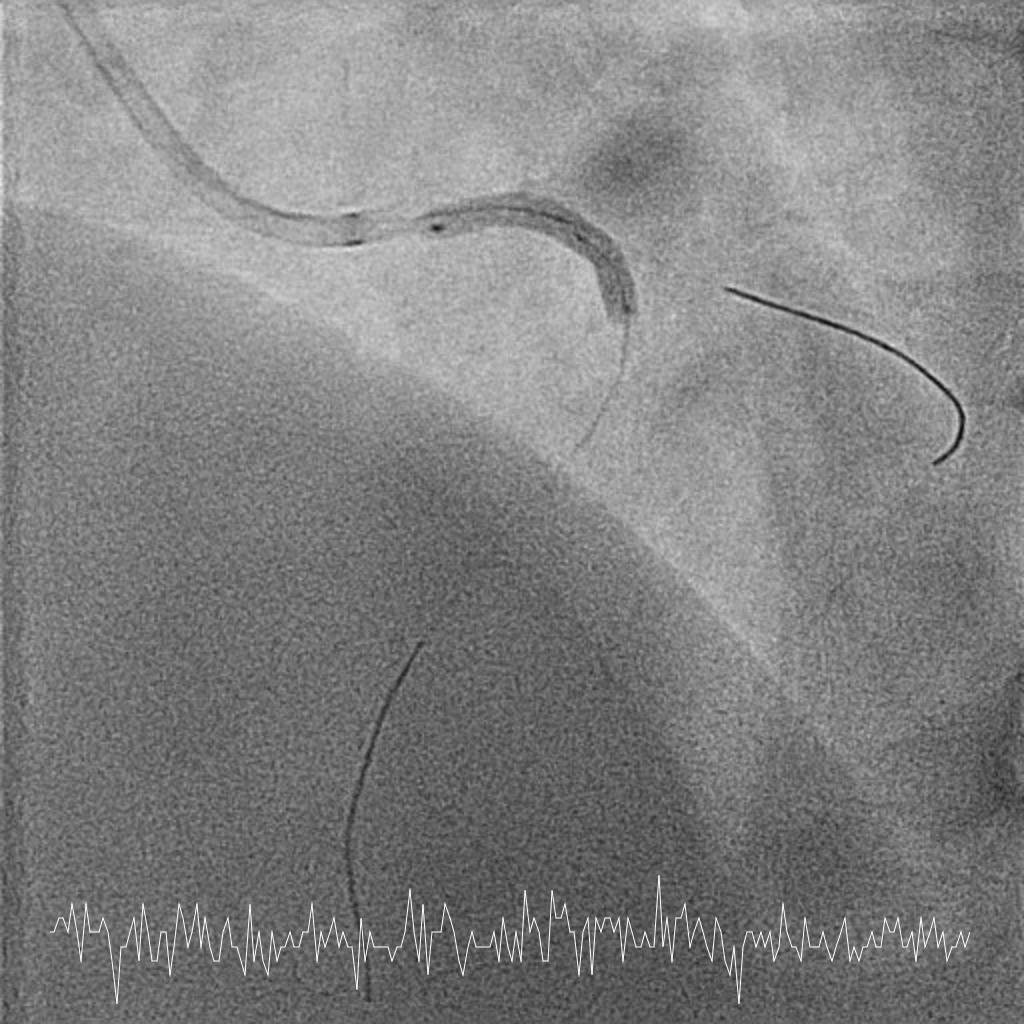

Femoral approach was chosen with a 7F sheath. A 7F JL4 guiding catheter was used for better support. JL4 was not coaxially engaged but positioned close to the ostial LM. Sion Blue ES was wired into LAD from the aortic cusp. A BMW wire was wired into LCx to provide additional support and as a safety wire in case of plaque shift into ostial LCx. Ostial LM was predilated with 3.0/10mm NC balloon at 12ATM which was delivered via Sion Blue ES with the guide and wire floating in the aorta. IVUS after predilatation revealed an ostial LM MLA 5.28mm2 with vessel size 4.0mm. Proximal LAD measured 3.0mm in size and exhibited fibrotic plaque with 70% plaque burden. Both ostial LM and proximal LAD were predilated with 3.0/15mm NC balloon delivered using the floating guide and Sion Blue ES. A 3.0/33mm DES was delivered and deployed with similar technique into proximal LAD using multiple projections for precise positioning to ensure proximal stent edge protrusion of 1-2mm into the aorta. POT of LM and ostial flare were performed using 3.75/15mm NC balloon. Proximal LAD was postdilated with 3.0/15mm NC balloon. IVUS confirmed a well-opposed stent without stent edge dissection. The final ostial LM MSA was 9.7mm2, with stent protrusion (1.7mm) into the aorta (less than one quadrant). The entire ostial LM was covered with stent struts.